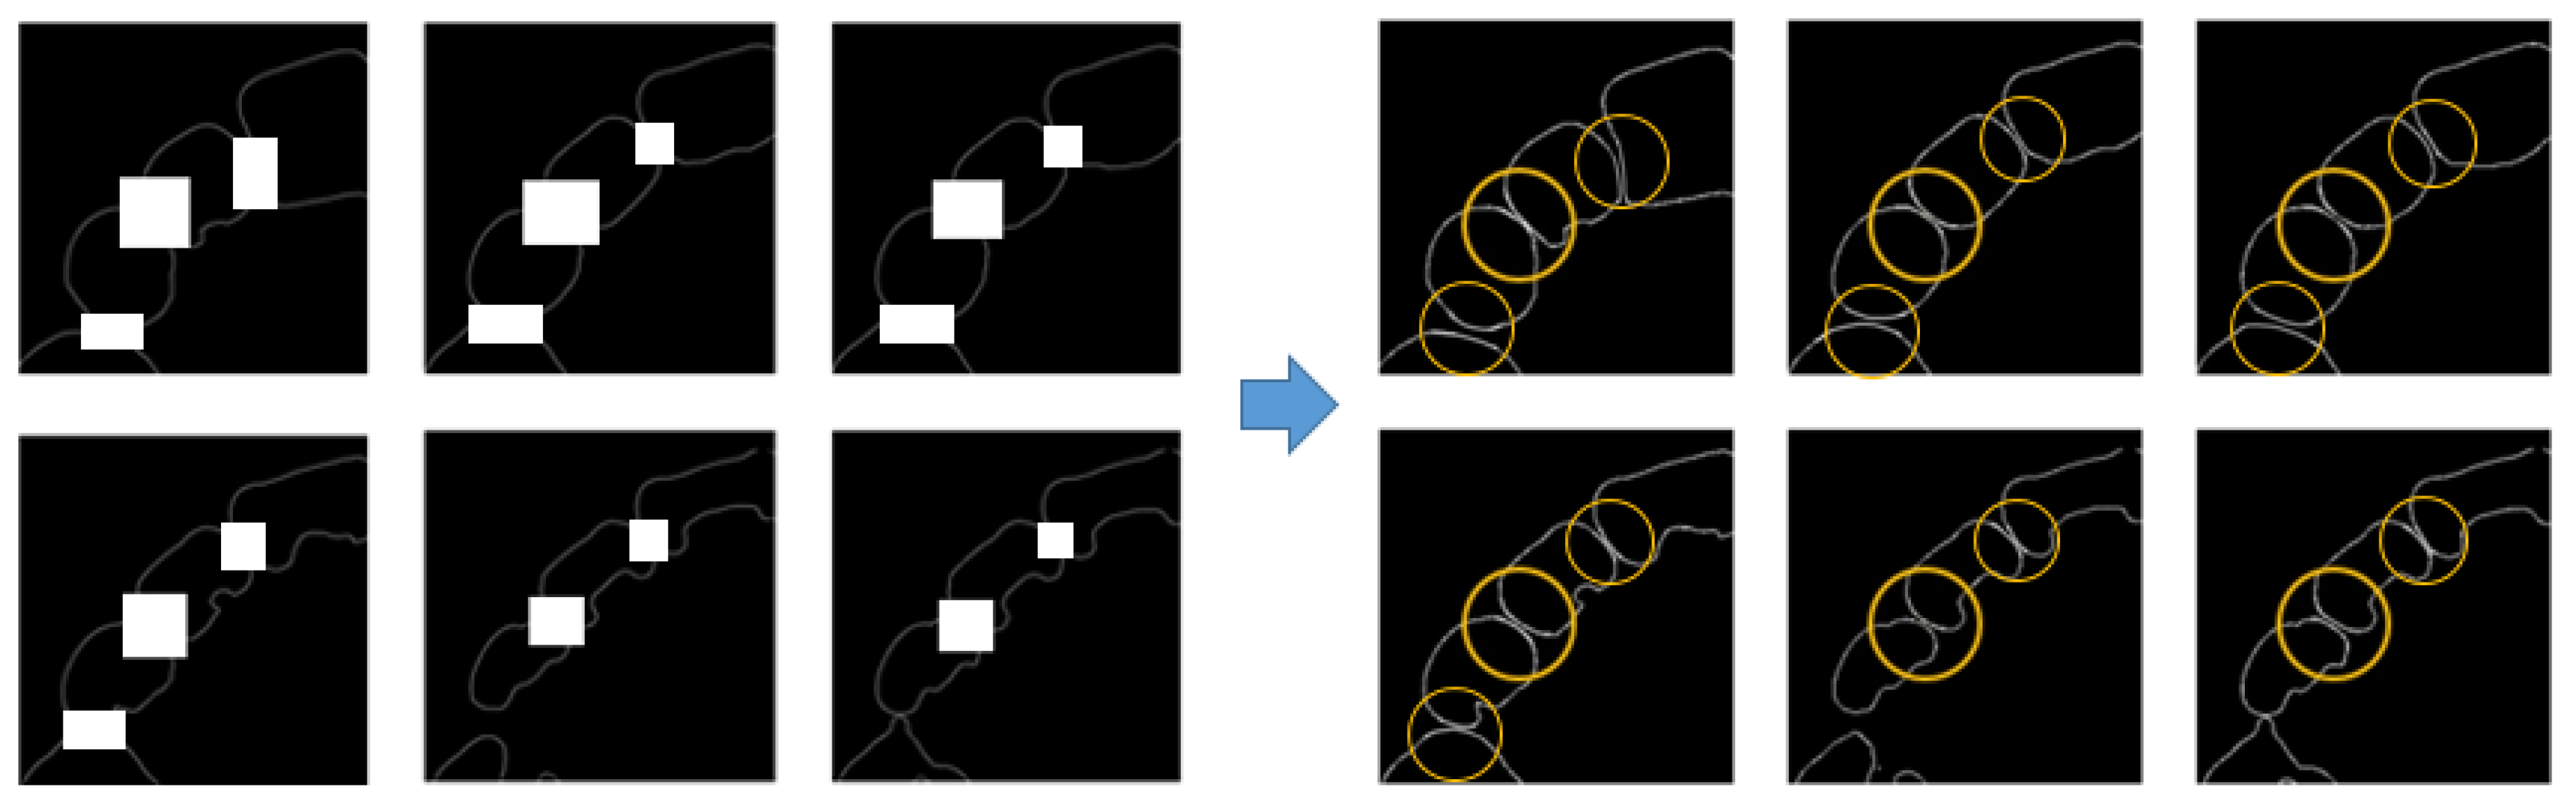

2.3.1. Data Preparation

2.3.2. Training Steps

3.1. Result of Image Completion